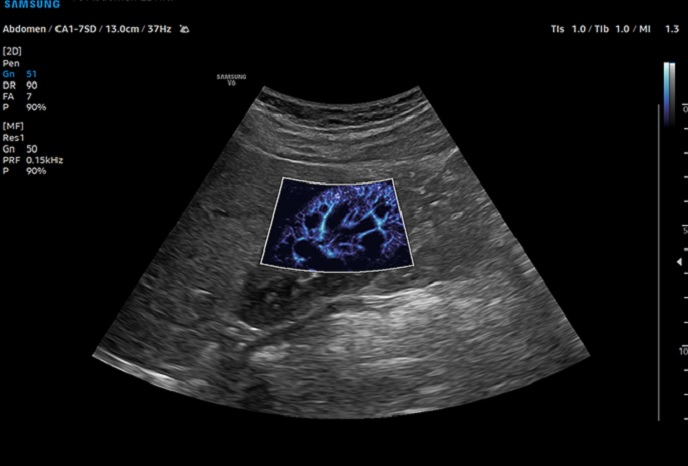

하이앤드 초음파 장비를

활용한 정밀 심장 검사

심장 질환 진단에서 가장 중요한 것은 ‘심장의 상태를 얼마나 정확하게 볼 수 있느냐’입니다. 저희 센터는 대학병원급 하이앤드 초음파 장비를 도입하여, 실시간 3D 렌더링으로 정밀 진단이 가능하며, 심장의 구조·혈류·기능을 실시간 고해상도로 관찰합니다.

미세한 판막 움직임, 혈류 속도 변화, 심방·심실 크기와 수축력까지 정밀하게 분석할 수 있어, 심장질환의 조기 발견과 치료 계획 수립에 큰 차이를 만듭니다.